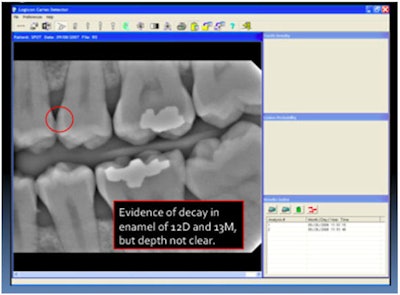

Here is an example of the Logicon Caries Detection software by Carestream Health/Kodak Dental Systems. The initial image gives the hint of caries on the mesial of No.13.

![]() |

| All images courtesy of Kodak and Cyber Medical Imaging. |